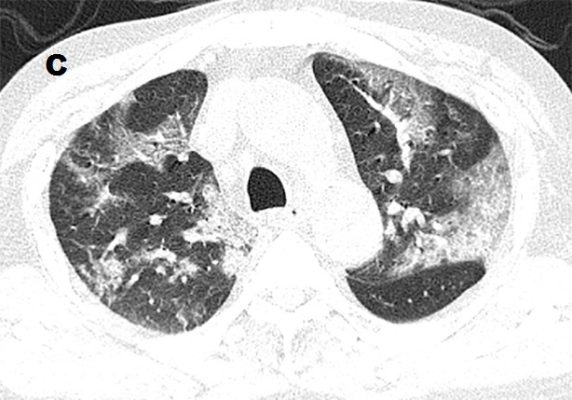

+ Hầu hết các báo cáo cho thấy thương tổn thể hiện bởi hình ảnh đám mờ với các hình thái: từ dạng kính đục đơn thuần (hình 1a)-loại này là nổi trội trong giai đoạn sớm, đến đám mờ dạng kính đục có biểu hiện dày vách liên tiểu thùy, vách trong tiểu thùy, dày dạng lưới (hình 1b), đến đám mờ dạng kính đục kèm đặc phổi từng phần (hình 2A); đám mờ dạng đặc phổi đơn thuần (hình 1c). Đám mờ thường có hình dạng hình học; có một số trường hợp thì các đám mờ dạng kính đục hay đám mờ đặc phổi lại có dạng hình tròn hoặc có biểu hiện dấu halo đảo ngược (dấu hiệu để chỉ thương tổn gồm viền đặc phổi dày tối thiểu 2 mm bao quanh vùng kính mờ ở trung tâm). Một kiểu thương tổn khác là dải mờ gặp với tần suất ít hơn (bảng 1).

+ Ngoài ra còn có một các dấu hiệu khác như: lớn ra của cấu trúc mạch máu bên trong đám mờ thương tổn (hình 2B), dày vách liên tiểu thùy và trong tiểu thùy tạo nên hình ảnh lát đá không đều (hình 1b, 2A), hình cây phế quản khí (hình 2A), dấu halo đảo ngược.